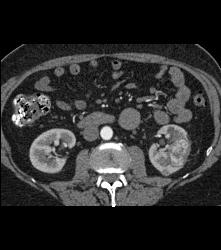

CASE NUMBER 4,532

Hypervascular Left Renal Cell Carcinoma